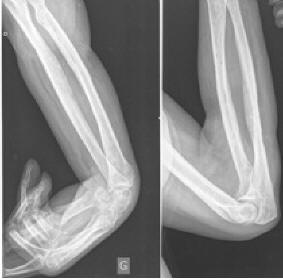

Volkmann's contracture - Wikipedia, The Free Encyclopedia

Volkmann's contracture, also known as Volkmann's ischaemic contracture, is a permanent flexion contracture of the hand at the wrist, resulting in a claw-like deformity of the hand and fingers. ... Read Article

Volkmann’s ischemic contracture Ischemic muscle contracture (flexion contracture) attributable to external pressure causing irreversible necrosis of muscle tissue, usually seen in the hand, resulting in claw hand, and most frequently observed in children ... Document Retrieval